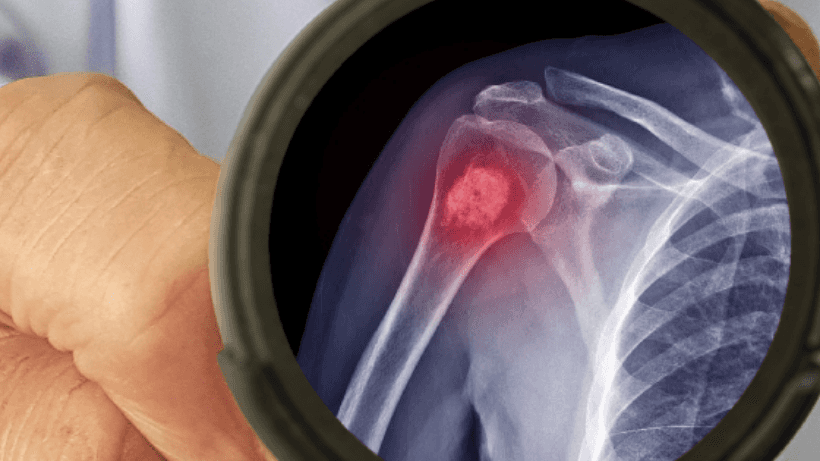

How is bone cancer diagnosed?

Once you experience symptoms and visit a doctor, your doctor will examine you to identify the problem and recommend various tests to confirm the diagnosis of bone cancer such as x-ray, bone scans, bone biopsies, CT scans, etc.